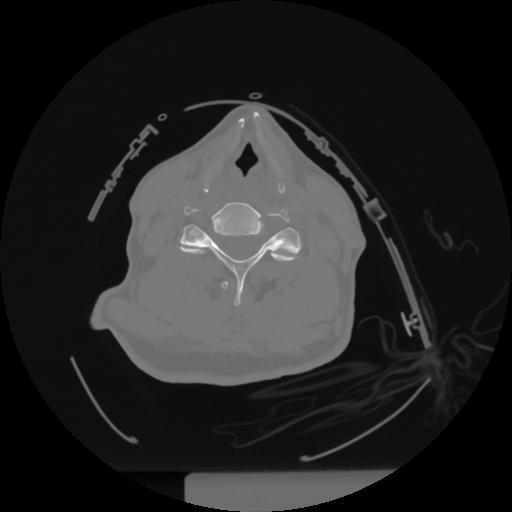

12 P.BLANDAS,,Vol,0.5,P.BLANDAS,,